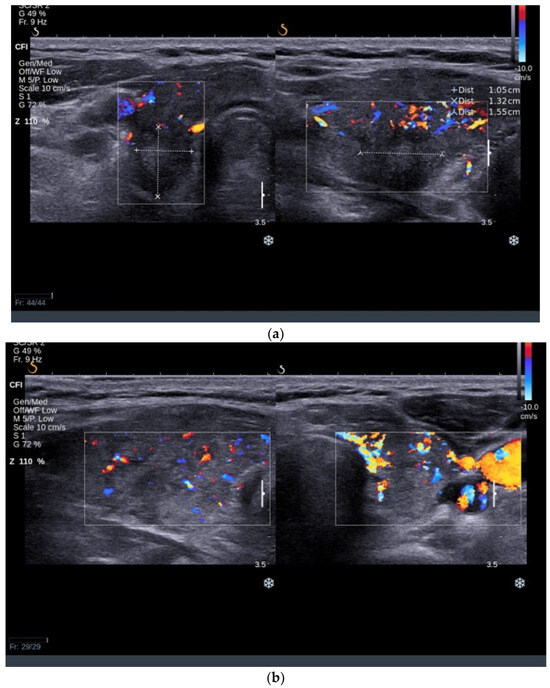

3.1.2. Thyroid Ultrasound

3.2.2. Thyroid Ultrasound

3.3.2. Thyroid Ultrasound